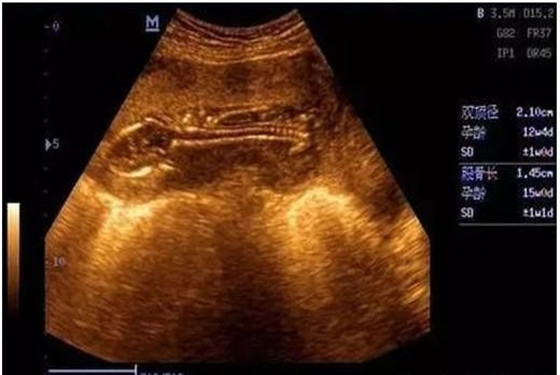

一般来说,B超单上的数据有很多,比如双顶径、腹围、股骨长、胎囊、胎心次数等,还可以从B超中观察到胎盘、羊水、脐带、胎儿脊椎等情况。老一辈有些人的说法认为看怀孕40-50天时的B超单,观察孕囊的大小和形状就能看出胎儿的性别,孕囊形状是椭圆或圆形的是女宝宝,长条形的是男宝宝。

1、7W+1D的BC数据: 胎囊2.9*1.9,生的是男胎儿。

2、60天的BC数据:孕囊大小是3.6*1.6MM,生下的是男胎儿。

3、5W+6D,孕囊:25mm*11mm,是男胎儿。

4、8周多是的BC,胎囊是19MM*10MM,后来BC照出来也是男胎儿。

5、62天,内见孕囊2.6*1.8,生的是可爱的男胎儿。

6、孕囊33*18 现B超是男胎儿。

7、孕囊长为44*20mm,生的是男胎儿。

8、9周+6天BC结果5.6*2.4 23周+5天BC看出是男胎儿。

9、7周多的B超数据,宫内见3.8*2.3CM妊娠囊,生的是男胎儿。

10、3.3*2.0cm生的是可爱的男胎儿。